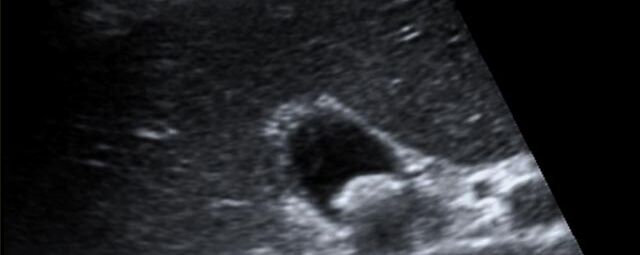

Die Sonographie ist ein bildgebendes Verfahren in der medizinischen Diagnostik, das mit Ultraschallwellen arbeitet. Ultraschall ist Schall mit einer Frequenz oberhalb der menschlichen Hörgrenze. Im medizinischen Bereich werden je nach Körperregion Ultraschallwellen in einem Frequenzbereich von ca. 3,5 – 18 Mhz verwendet. Die körpernahe Ultraschallsonde sendet durch einen piezoelektrischen Effekt kurze Schallwellenimpulse in den Körper. Ultraschall-Gel stellt den Kontakt zwischen Sonde und Körper her. Je nach Gewebeart werden diese Schallwellen im Körper unterschiedlich stark reflektiert. Anhand des zurückgesendeten Schallmusters kann das Ultraschallgerät Schnittbilder berechnen, auf denen die Organe des Körpers nach krankhaften Veränderungen untersucht werden können.